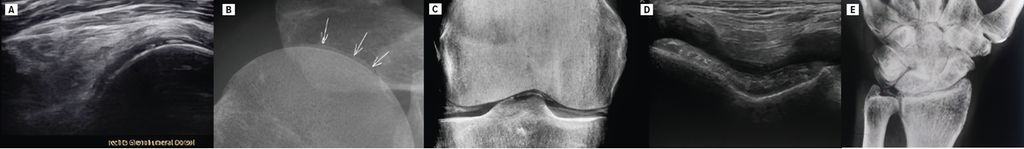

Bei einem polymyalgischen Syndrom sollte immer an eine Kalziumpyrophosphaterkrankung (CPPD) gedacht werden. So ist die Prävalenz der CPPD mit 5% noch höher als die der PMR mit 1%.4 Bei der CPPD (auch Pseudogicht genannt) kommt es zur Ablagerung von Kalziumpyrophosphat-Dihydrat in kristalliner Form in Knorpel, Gelenken, Ligamenten, Sehnen und Bursen. Diese Ablagerungen können in Form von Verkalkungen im konventionellen Röntgen und im Ultraschall der Gelenke festgestellt werden (Abb.1). Dieser röntgenologische Befund, der bei 15% der >60-Jährigen auch asymptomatisch gefunden werden kann, wird als Chondrokalzinose bezeichnet. Typischerweise finden sich Ablagerungen am Schultergelenk (am hyalinen Knorpel des Humeruskopfs und am Faserknorpel des Labrum glenoidale sowie des AC-Gelenksdiskus), am Hüftgelenk (am Faserknorpel des Labrum acetabuli), am Kniegelenk (am hyalinen Knorpel von Femur und Tibia, am Faserknorpel der Menisken) sowie an den Handgelenken am Faserknorpel des Discus triangularis («triangular fibrocartilage complex», TFCC). Auch eine dominante STT-Arthrose bei vergleichsweise geringer Rizarthrose, Osteophyten an den MCP(metakarpophalangealen)-2- und -3-Gelenken der Finger sind typische Zeichen im Röntgen und Ultraschall. In selteneren Fällen kann auch die Halswirbelsäule betroffen sein mit Verkalkungen am Ligamentum transversum atlantis um den Dens axis, was zum Bild eines sogenannten «crowned dens syndrome» mit akuten Nackenschmerzen führen kann. In 20% der Fälle finden sich im Röntgen keine Verkalkungen im Sinne einer Chondrokalzinose. Sensitiver ist die Suche nach Kalziumpyrophosphat-Kristallen in der Synovialflüssigkeit, sodass im Falle eines Gelenksergusses, wann immer möglich, eine diagnostische Gelenkspunktion erfolgen sollte.

Abb. 1: Röntgen und Ultraschallbilder von Patienten mit Kalziumpyrophosphaterkrankung als wichtigste Differenzialdiagnose der Polymyalgia rheumatica. Verkalkungen im hyalinen Knorpel des Humeruskopfs in Ultraschall (A) und Röntgen (B); Verkalkungen im hyalinen Knorpel des Femurs sowie im Faserknorpel des Meniskus im Röntgen (C) und im hyalinen Knorpel des Femurs im Ultraschall (D); Verkalkungen im Discus triangularis («triangular fibrocartilage complex», TFCC) im Röntgen (E)